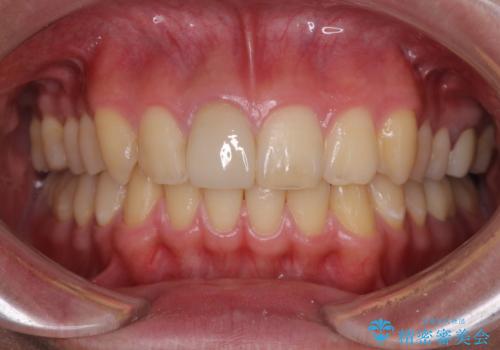

矯正治療中に上下前歯が接触しない時期があり、咬み合わせ改善のために期間がかかるのではないかと懸念されましたが、結果的には補綴治療も含めて1年以内の短期間で終えることができました。